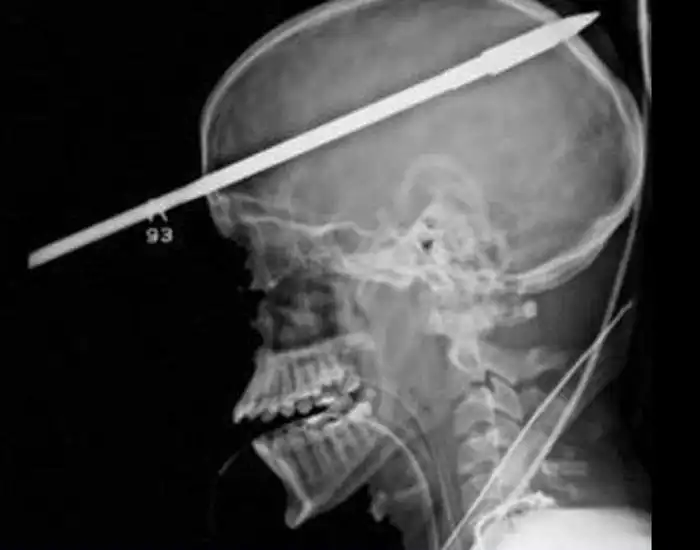

На рентгеновских снимках людей порой можно обнаружить самые необычные предметы, которые находятся в их теле.